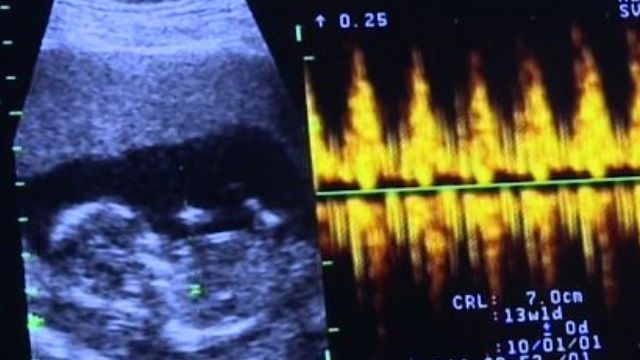

超音波影像可聽到小寶寶的心跳聲,可是洪小姐期盼了好久才終於等到他,不過寶寶不是在自己的肚子裡,而是遠在美國一名代理孕母的肚子中,生殖中心醫師 王懷麟:「她其實非常興奮,因為她知道說她多年擁有小孩的夢想,終於可以完成,所以當她看到心跳的聲音還有影像,她覺得非常難以接受這樣的事實,但是她很期待。」